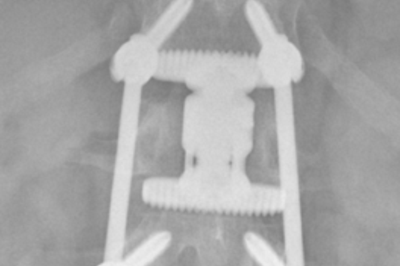

• Verschraubter Wirbelbruch

Röntgenbild verschraubter Wirbelbruch